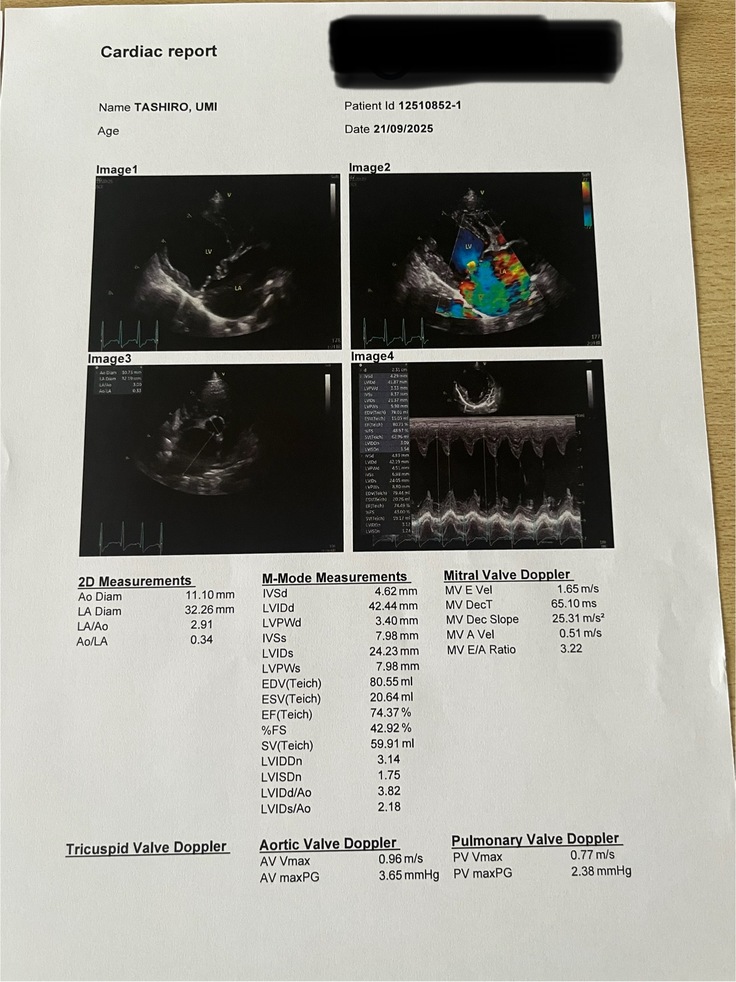

2025.9.21 かかりつけ医から9/20に外科的手術が出来る病院に紹介の連絡を入れて頂き、青海の症状かなり悪い為、翌日に緊急に受診することが出来ました。到着してすぐ先生が確認しそのまま酸素室へ、専門医の診断は、最低ランクのステージDこのままでは、1か月持ちません。救命のためには手術以外の選択肢はないと。追加の入院費か高いですがこのまま帰ったら危険です。酸素濃度50%の酸素室で24時間体制で管理しています。入院して手術にキャンセルが出た時、または予備日に手術をするという事で、入院し9/24 無事に手術を受けることができました。